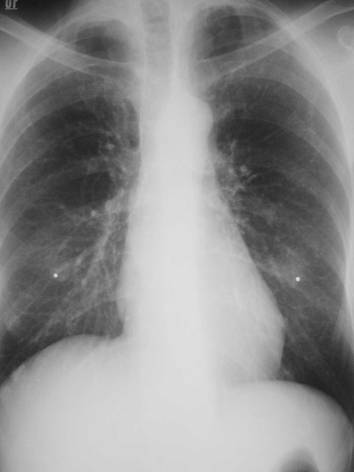

Nipple shadows